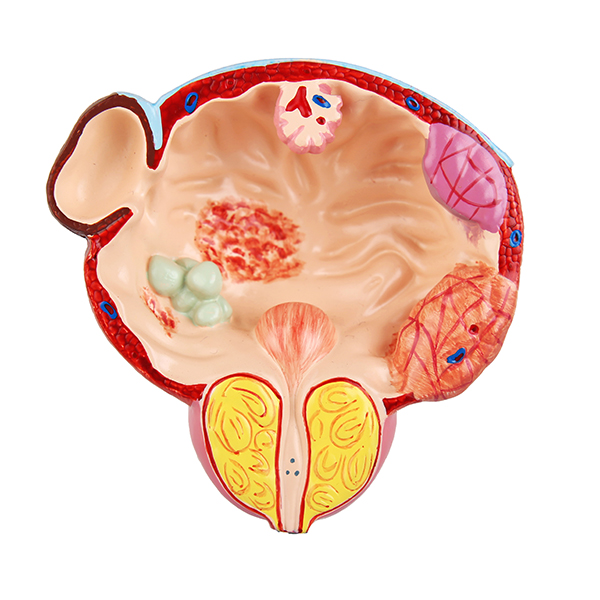

在探討海芙刀這項革新技術之前,我們必須先理解將這股浪潮引入台灣的第一人,鄭丞傑醫師。他不僅是一位日復一日面對病患的資深婦科醫師,其影響力更已擴展至亞洲乃至全球的消融醫學領域。

這份權威性,建立在他於專業領域的實際貢獻之上:

在台灣:作為台灣婦科腫瘤消融醫學會的創會理事長,他主導建立了本土的學術交流平台,透過舉辦年會與國際研討會,凝聚專家共識,致力於提升國內的治療水平與標準化。

在亞洲:擔任亞太婦科腫瘤消融學會理事長,他積極促進亞太各國醫師間的技術合作與經驗分享,鞏固了台灣在該領域的樞紐地位。

在全球:出任世界消融醫學會的婦科委員會主席,他更代表著婦科專業,在國際舞台上分享來自台灣的臨床數據與成功經驗,參與全球性的學術對話。

正是這份橫跨臨床、區域與世界的宏觀視野,讓鄭醫師能遠在十多年前便洞見婦科治療的未來趨勢。本篇文章,將帶您深入了解他如何將這份遠見化為真實的醫療服務,並透過「海芙刀」為無數女性開創了保留子宮、遠離手術恐懼的嶄新選擇。